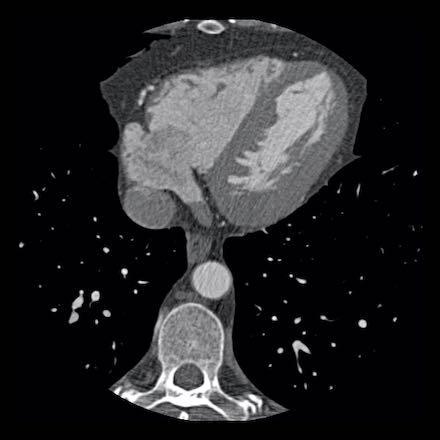

case 3 – Calcium score 0 and severe stenoses.

First, scroll through the CTA images.

How would you describe the findings on the coronary CTA?

The findings are:

- The total calcium

score of 0 indicates the absence of calcified plaque in the coronary

tree. - Severe stenosis

(70-99%) in the mid LAD and D2 branch.

Continue with the next images of the same patient…